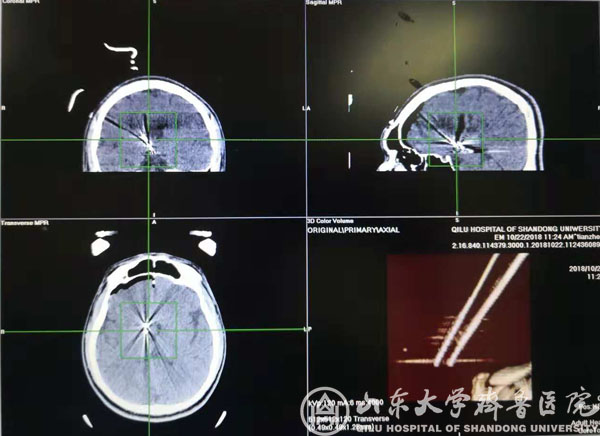

术前计划

术中CT验证靶点

该患者男,20岁,发作性头痛、痴笑、左眼向上凝视病史11年,口服丙戊酸钠、拉莫三嗪、鲁米那等多种抗癫痫药物效果欠佳,每日痫性发作仍3~6次,颅脑MRI提示右侧丘脑前下部占位性病变,考虑下丘脑错构瘤。患者收入我院功能神经外科病房后,赵秀鹤副主任带领神经内外科团队共同对患者进行了充分的术前评估,对手术方案进行了深入的讨论,考虑到病变位置重要且深在,开放性开颅手术风险高,术后并发症发生率高,最后决定采用立体定向脑电图引导下射频热凝术的治疗方案。10月21日,徐淑军主任、徐硕主治医师为患者制定了SEEG方案,并在手术机器人引导下成功将颅内电极埋藏在预设手术靶点。经术中CT、多模态影像融合技术以及立体定向脑电监测等多种手段验证靶点后,对致痫灶实施精准射频热凝。术后患者癫痫发作频率较术前减少,未见明显不良反应,已顺利出院,长期疗效正在随访观察中。